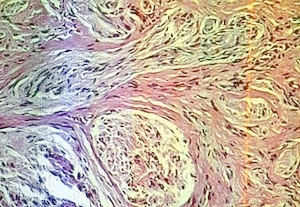

Read MoreNevus_comedonicus = الوحمة الزؤانية Nevus Comedonicus A nevus comedonicus consists of closely set, slightly elevated papules that have in their center a dark, firm, hyperkeratotic plug resembling a comedo. Nevus comedonicus, like linear epidermal nevus, usually has a linear configuration and occurs as a single lesion. In some instances, however, there are multiple bilateral linear […]